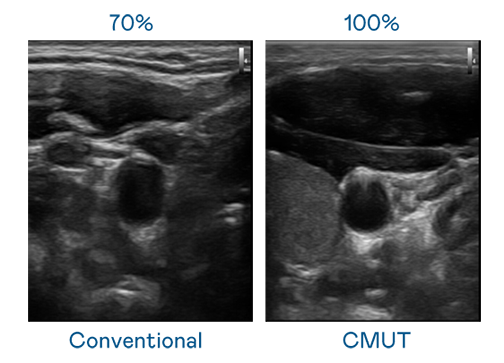

CMUT 技术是一种用电容式微机电元件来产生超音波讯号的技术。与传统 PZT 压电式技术相比,CMUT 频宽增加 30%,更宽频的超音波讯号让影像解析度大幅提升,是实现高影像品质医疗超音波扫描、促进精准医疗发展的关键技术。

大频宽带来超清晰影像

超音波影像的解析度高低,首先取决于探头能发出的讯号频宽。部落先锋 CMUT 可提供高清晰的超音波讯号,提供高频宽、高灵敏度、影像纹理细节更高的超音波影像,协助医护人员缩短影像判读时间及利用精准的医疗影像进行诊断。